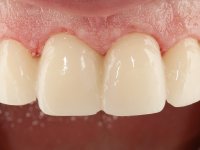

Realizado o diagnóstico e tomada a decisão quanto ao tratamento a executar, tornou-se importante definir qual a sequência de trabalho a adotar no sentido de conseguir a reabilitação da D.V.O. (V.D.O), de forma progressiva e equilibrada. Na primeira fase fez-se uma pré-impressão da arcada inferior com silicone tipo “putty” e em seguida realizou-se o preparo dentário de todo o sector posterior. O preparo para os overlays foi feito coronalmente à linha amelo cementaria no sentido de ser o mais conservador possível. A impressão foi feita com técnica de dupla mistura após afastamento gengival realizado com pasta de caulino. A provisória foi realizada com resina composta de polimerização dual. Em laboratório foram realizados os overlays após se ter aberto ligeiramente (1,5mm) a D.V.O. nos modelos montados em articulador semi-ajustável. Simultaneamente o sector antero-inferior foi encerado no sentido de acompanhar este aumento da D.V.O. Também foi confecionada uma chave de silicone translucido para posterior confeção dos provisórios antero-inferiores. Em boca foi primeiro realizada a provisionalização dos dentes anteriores utilizando resina composta previamente aquecida após preparação das superfícies dentárias para a adesão. Foi colocado o dique de borracha para promover o isolamento absoluto e posteriormente foram colados os overlays. Em laboratório foi realizada nova chave de silicone para confecionar os provisórios antero-superiores. Seguidamente em boca foram preparados os seis dentes antero-superiores após colocação do fio de afastamento gengival. Feita a preparação adequada das superfícies dentárias foi realizada a impressão com técnica de dupla mistura e a respetiva provisória. Em laboratório foram confecionadas 6 facetas feldespáticas num modelo de trabalho tipo “Geller”. A provisória foi removida e as facetas foram coladas em boca utilizando um isolamento relativo competente. Esta opção foi tomada em virtude de uma prévia experiencia negativa com a colocação do dique de borracha na mandibula. Após a colagem dos laminados antero-superiores foram dadas 12 semanas para avaliar a adaptação do paciente à nova situação e então iniciar a confeção das facetas antero-inferiores. Após colocação do fio de afastamento gengival. foram feitos os preparos dentários adequados e em seguida foi feita a impressão. Também foi feita a preparação do dente 3.4 que, entretanto, tinha sofrido uma fratura do overlay. As facetas e a restauração do 3.4 foram realizadas num modelo de trabalho tipo “Geller”. Após remoção da provisória, as facetas foram coladas em boca, utilizando um isolamento relativo pelas razões apontadas anteriormente. Após colocação do trabalho o paciente foi reabilitado por outros colegas com um implante na zona do 2.6 e substituição da coroa aparafusada sobre o implante colocado no local do 3.5. Posteriormente surgiram fraturas nos overlays dos dentes 4.7 e 3.7 que foram reabilitados com overlays em Zr.